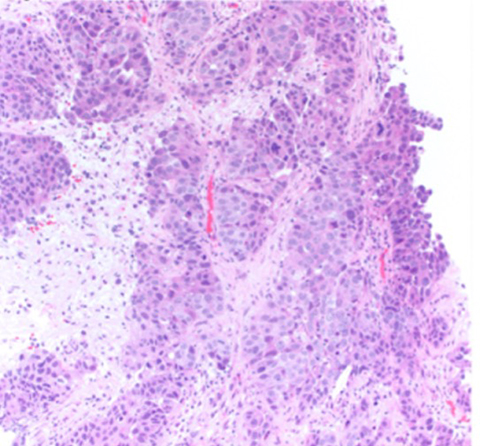

Figure 2: H&E Image of the Submandibular Mass Biopsy

The excision of the submandibular mass was diagnosed at the third institution as a salivary gland adenocarcinoma NOS with the differential diagnosis of the biopsy including CXPA. The excision was not sent for NGS or otherwise tested for PLAG1 alterations. Immunohistochemistry performed on the biopsy was positive for p16 and in-situ hybridization was negative for HPV. This case highlights a potential diagnostic pitfall of relying on p16 immunostaining to make a diagnosis of squamous cell carcinoma in limited biopsy materials or metastasis while simultaneously highlighting the potential clinical benefit of ancillary molecular testing in limited or poorly differentiated specimens. Although perhaps more salient, this case demonstrates the necessity for more effective communication and portability of pathology results across institutions that patients visit to prevent misdiagnosis and the need for additional testing.